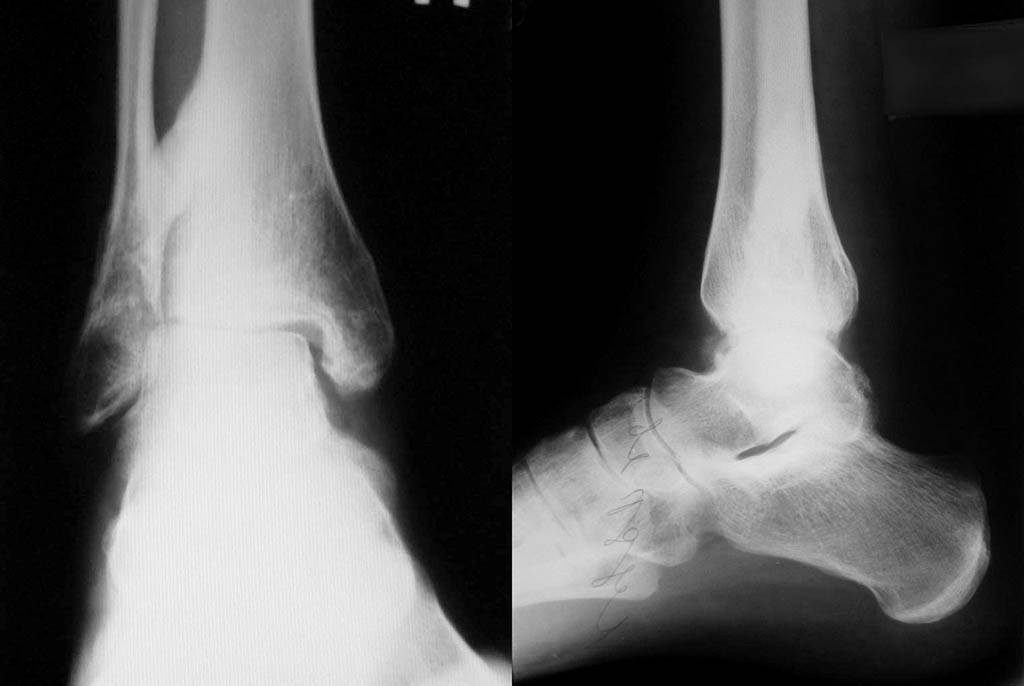

Re: Застарелое повреждение голеностопа

Приложил последние снимки г/стопа.

Сустава-то нет. Артродез.

Мы с коллегами тоже склояемся к такому исходу. У пациента стойкое желание сохранить сустав. Хотя пациент довольно вменяемый, образованый молодой человек. Возможно согласится.